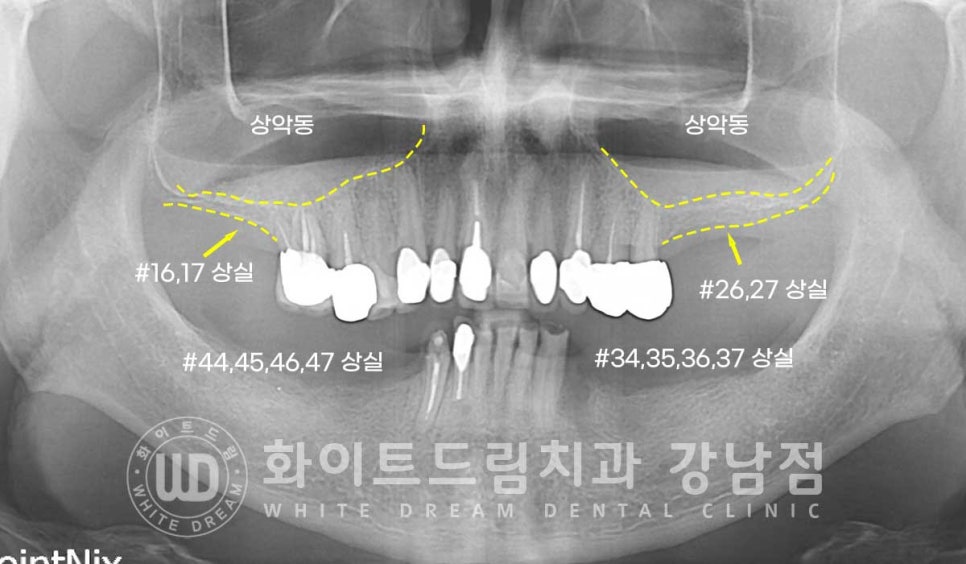

임플란트 개수를 줄여, 치료를 받으신 환자분의 치료 사례입니다.

상/하 양쪽 어금니가 모두 상실된 상태로 어금니 부분 틀니를 이용하여

상악은 오랜 기간 치아가 없는 채로 생활을 해오셨기에 잇몸뼈 흡수가 심하게 진행된 상태였습니다.

상악 어금니 부분은 길이 8.5mm 직경 4.5mm의 임플란트가 들어갈 만큼의

잇몸뼈가 없는 상태로 상악동의 얇은 막을 살짝 들어 올린 후

임플란트 식립을 진행하는 상악동 거상술을 동반하였고

하악은 신경관과의 거리가 안정적으로 유지되기에 추가적인 뼈이식만 동반하여

임플란트 식립을 진행하기로 했는데요.

환자분의 상악동 거상 술 전의 잇몸뼈 높이와 거상 후를 비교해 보면

한눈에 어떤 부위에 대량의 뼈이식이 진행됐는지 확인하실 수 있을 겁니다.

노란색 점선이 초기 환자분의 잇몸뼈 높이이며, 거상 후 하늘색 선 만큼 상악동이 올라갔고

그 사이에 하얗게 보이는 뼈이식재가 들어간 것이 확인됩니다.